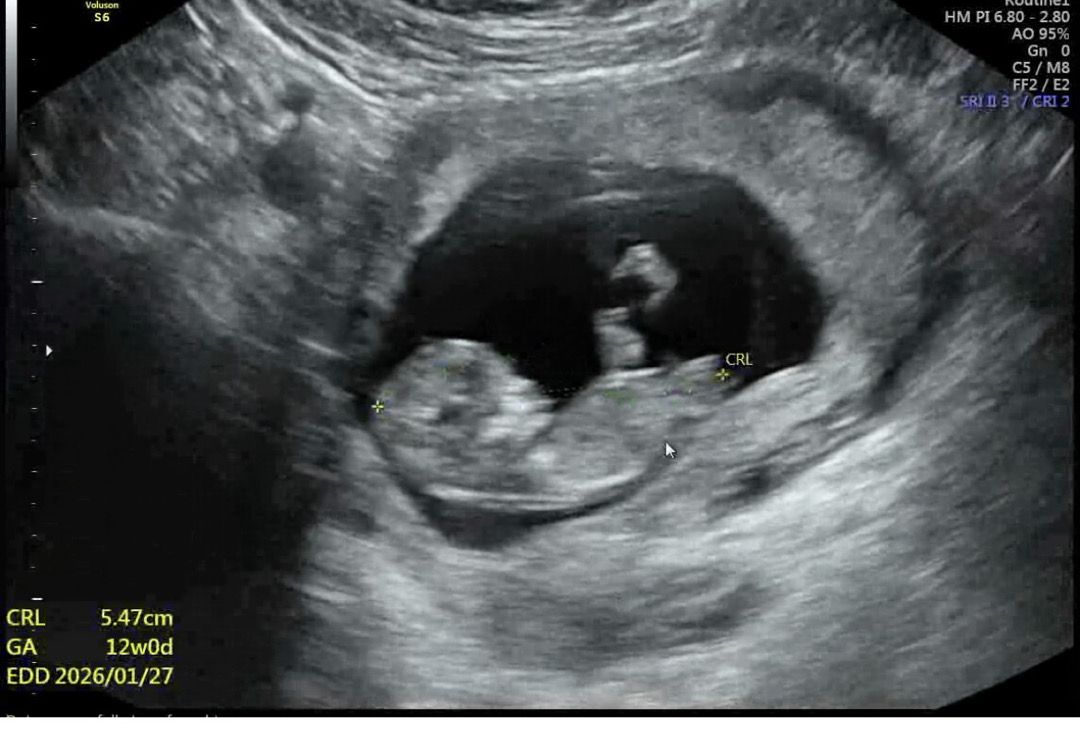

각도법 봐주세요〰️💟

오늘 보고왓는데 넘나 궁금하네여^^